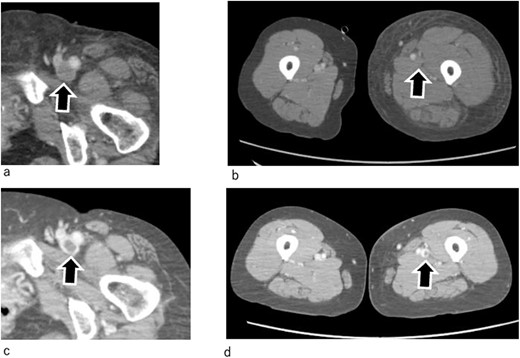

By Day 2 of hospitalization, the pale skin of the patient and pain started to improve, and she was able to move her left lower extremity (Fig. 1b). Enhanced computed tomography (CT) revealed the resolution of the thrombus in the GSV; however, the deep veins remained completely occluded by thrombi (Fig. 3a and b). An ultrasound arteriogram revealed normal arterial blood flow.

Enhanced CT. (a, b) One day after admission. The thrombus in the GSV has disappeared. However, thrombi are still observed in the deep veins, which remain totally occluded. (c, d) On Day 7. The thrombi in the deep veins have shrunk, and the veins have recanalized. Arrow marks indicate femoral veins.

On Day 9 of hospitalization, the leg swelling resolved. Contrast-enhanced CT revealed partial recovery of blood flow in the deep veins (Fig. 3c and d). In addition, the swelling of the left lower extremity resolved (Fig. 3b and d). Following this, heparin was changed to the oral anticoagulant apixaban (10 mg/d).